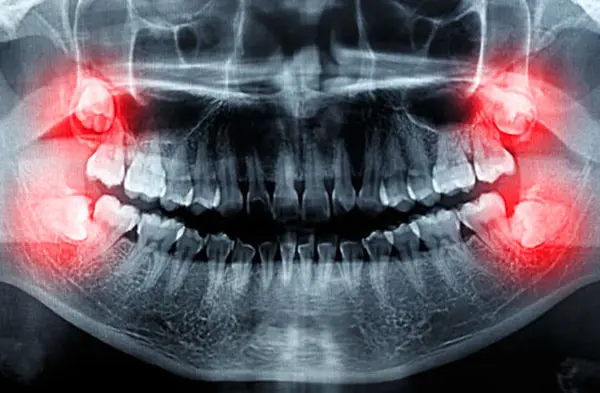

چند توصیه برای تسریع بهبودی پس از جراحی دندان عقل

دندانهای عقل، دندانهای بزرگی هستند که در بیشتر افراد بین سنین ۱۷ تا ۲۵ سالگی در انتهای دهان رشد میکنند اما ممکن است برخی افراد دندان عقل نداشته باشند.

در برخی موارد لثه جای کافی برای رشد دندانهای عقل ندارد که باعث میشود این دندانها به صورت نصفه یا با زاویهای نامناسب رشد کنند و باعث بروز مشکلاتی مانند درد یا عفونت شوند.